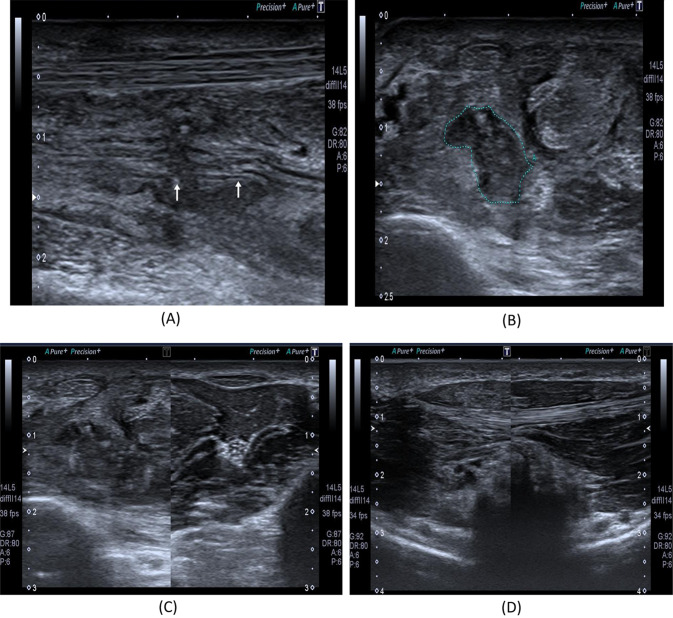

Fig. 1.

An 18-year- old male with a history of a cut wound of the right forearm since September 2021 and tendon repair, sensory loss of the skin on the radial aspect of the palm with skin ulceration. A B-mode image shows a discontinuous right median nerve at the mid-forearm with related hypoechoic tissue suggesting complete nerve injury proved by NCS. B B-mode image shows a transverse axis view at the site of the lesion showing a hypoechoic area with non-visualized nerve tissue. C B-mode image shows a comparison between the right and left mid-forearm muscles. The right side shows an abnormal architecture of the FDS and FDP muscles with increased echotexture as compared to the left normal side. D B-mode image shows a comparison between the right (left image) and left (right image) thenar muscles. The right side mildly increased echotexture as compared to the left normal side with rather preserved girth